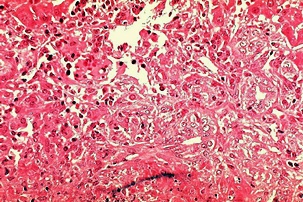

몸에 필요한 황색의 담즙색소 (빌리루빈)이 과도하게 쌓여 눈동자나 피부 등에 착색되는 현상을 말한다고 합니다. 이 담즙색소는 체내에 들어온 물질들이 분해되는 과정에서 생성되는 필요 없는 물질인데요. 일반적으로는 간에서 해독작용을 거친 후에 담즙으로 배설이 되는 것이 정상적이지만, 그렇지 못한 경우 황달이 발생하게 된다고 합니다.

황달이 생기는 이유는 담즙색소라고 알려진 빌리루빈이 과도하게 생기기 때문입니다. 빌리루빈은 우리 몸의 오래된 적혈구가 파괴되면서 생기는 물질인데요. 이 물질은 담즙에 녹아서 우리 몸의 배설물과 함께 배출이 되는 것이 정상적이지만 빌리루빈의 과잉생산이나, 간의 장애, 간세포나 담도의 손상에 의해 빌리루빈이 역류할 경우 발생된다고 합니다.

황달이 생겼을 때 나타나는 대표적인 증상은 소변의 색깔이 진하게 변하는 것입니다. 이는 과도하게 분비된 빌리루빈이 소변으로 배출되기 때문인데요. 이러한 경우 소변의 색이 진한 갈색으로 변하게 됩니다. 또한 피부에 담즙색소가 침착되면 눈이 노랗게 변하는데요. 눈에 노랗게 된다고 모두 황달 증상을 의심할 수 있는 것은 아닙니다.